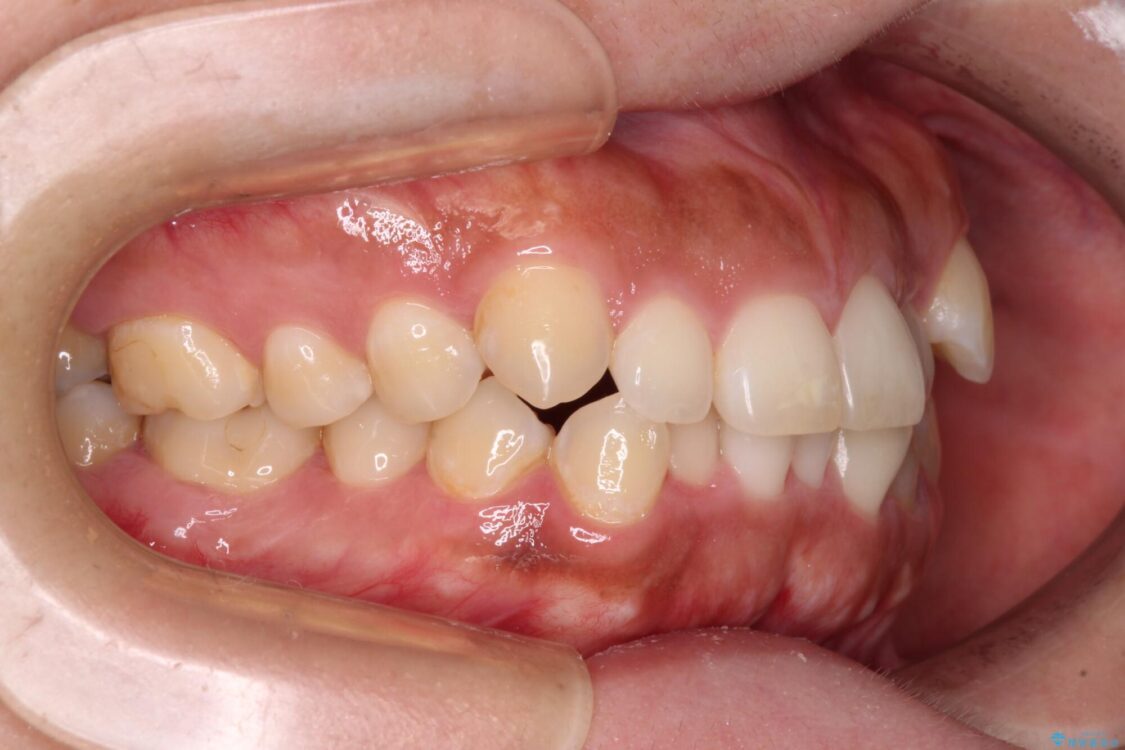

治療後

• 【モニター】カリエール・ディスタライザーを併用した八重歯のインビザライン矯正 治療後画像